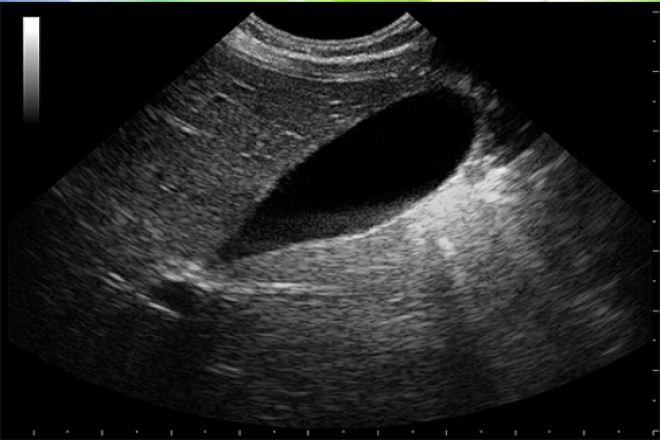

Exploración ultrasonográfica renal

La ultrasonografía del sistema urinario es una herramienta diagnostica de apoyo en el ejercicio de la profesión médica, pues permite un diagnóstico y tratamiento oportuno de las patología renales a través de la evaluación de las estructuras anatómicas del paciente mediante sonido. Además es un técnica que se puede usar